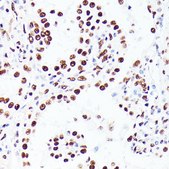

SAB5700065

Anti-PML antibody produced in rabbit

immunofluorescence: 1:50-1:200, immunohistochemistry: 1:50-1:200, western blot: 1:500-1:2000